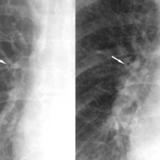

APE 2

Date: 11/05/2005

Views: 2684